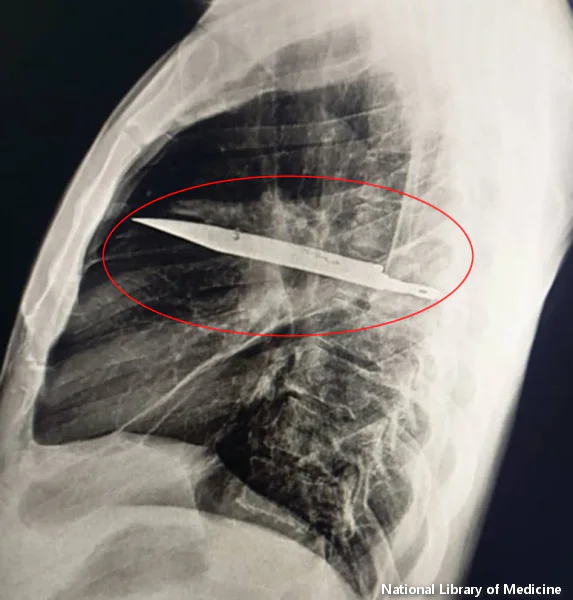

Ne uspevši da utvrde uzrok infekcije, lekari su naručili rendgenski pregled i bili su šokirani kada su videli džinovski nož zaglavljen u čovekovim grudima.

„Početno snimanje bočnim rendgenskim snimkom grudnog koša pokazalo je zadržani metalni predmet u srednjem delu grudnog koša, sa okolnim zamućenjem koje verovatno predstavlja rastući ili hronični lokulirani hematom ili posttraumatsku fibrozu, posledicu pacijentove ubodne rane“, napisali su lekari u svojoj studiji slučaja.

Nekako je sečivo noža, koje je ušlo kroz desnu lopaticu, čudesno uspelo da izbegne sve glavne organe.!